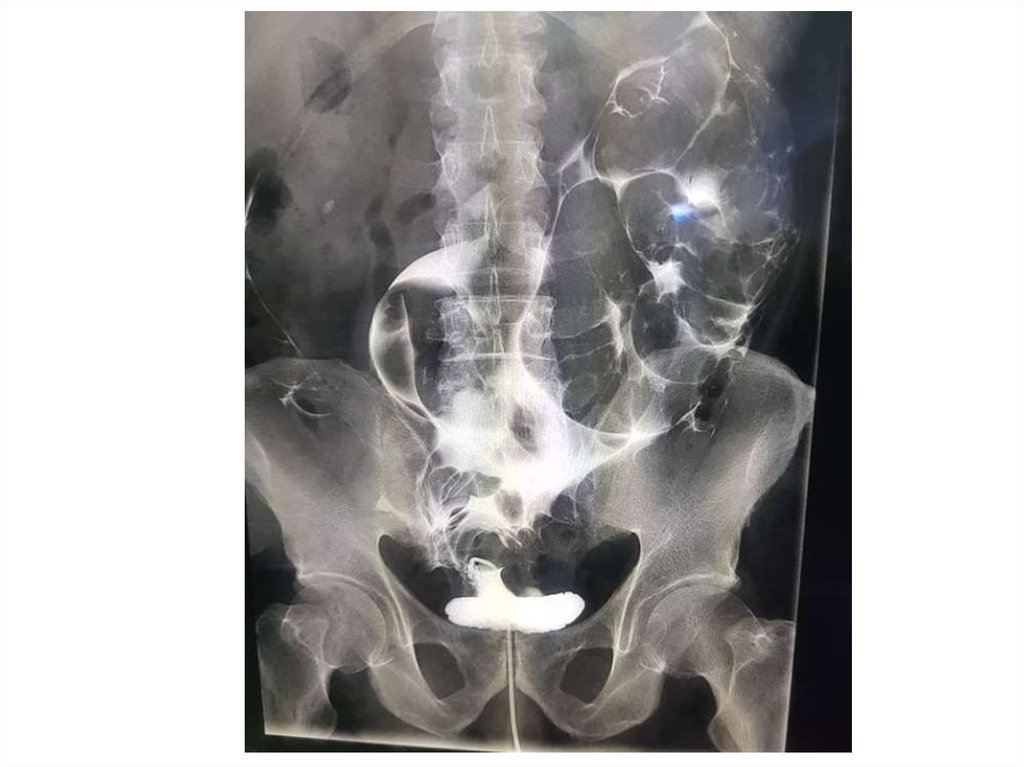

Назовите

• Вид исследования

• Область исследования

• Патологию